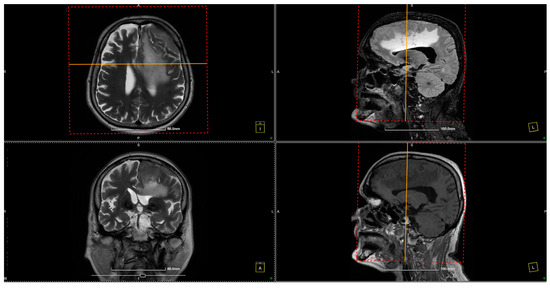

Further evaluation with contrast-enhanced MRI confirmed the presence of a tumoral mass, which was isointense with brain parenchyma on T1-weighted images and moderately hyperintense on T2-weighted images, with intense and homogeneous enhancement following contrast administration. Notable peritumoral cerebral edema was observed, extending to the interhemispheric region and the corpus callosum. The lesion appeared suggestive of a meningioma measuring 4 × 6 cm. The remainder of the brain appeared normal on T1- and T2-weighted sequences, as well as after contrast administration (Figure 1 and Figure 2).

Figure 1. Preoperative MRI. The preoperative MRI scans display a large, convexity en plaque meningioma in the left frontoparietal region, extending toward the parasagittal area. The tumor exhibits homogenous enhancement on T2-weighted images, indicating a highly vascular lesion consistent with meningiomas. The tumor’s dimensions are approximately 4 × 6 cm, and it infiltrates the dura mater, extending deeply toward the paraventricular area. This infiltration reaches the superior sagittal sinus, posing challenges for surgical resection due to the involvement of this critical venous structure. The dashed frames indicate the area of interest, while the yellow lines mark intersecting planes across axial, sagittal, and coronal views, facilitating anatomical correlation and spatial orientation for surgical planning.

Figure 2. Preoperative MRI. The preoperative MRI scans illustrate a large, homogeneously enhancing convexity en plaque meningioma located in the left frontoparietal region. In these images, the tumor’s infiltration of the dura mater and partial involvement of the superior sagittal sinus are evident, posing additional complexity for surgical resection.